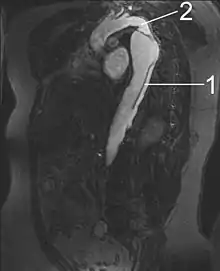

| Aortic dissection | |

Arterial dissections become life-threatening when growth of the false lumen prevents perfusion of the true lumen and the related end organs. For example, in an aortic dissection, if the left subclavian artery orifice were distal to the origin of the dissection, then the left subclavian would be said to be perfused by the false lumen, while the left common carotid (and its end organ, the left hemisphere of the brain) if proximal to the dissection, would be perfused by the true lumen proximal to the dissection.

Vessels and organs that are perfused from a false lumen may be well-perfused to varying degrees, from normal perfusion to no perfusion. In some cases, little to no end-organ damage or failure may be seen. Similarly, vessels and organs perfused from the true lumen but distal to the dissection may be perfused to varying degrees. In the above example, if the aortic dissection extended from proximal to the left subclavian artery takeoff to the mid descending aorta, the common iliac arteries would be perfused from the true lumen distal to the dissection but would be at risk for malperfusion due to occlusion of the true lumen of the aorta by the false lumen.